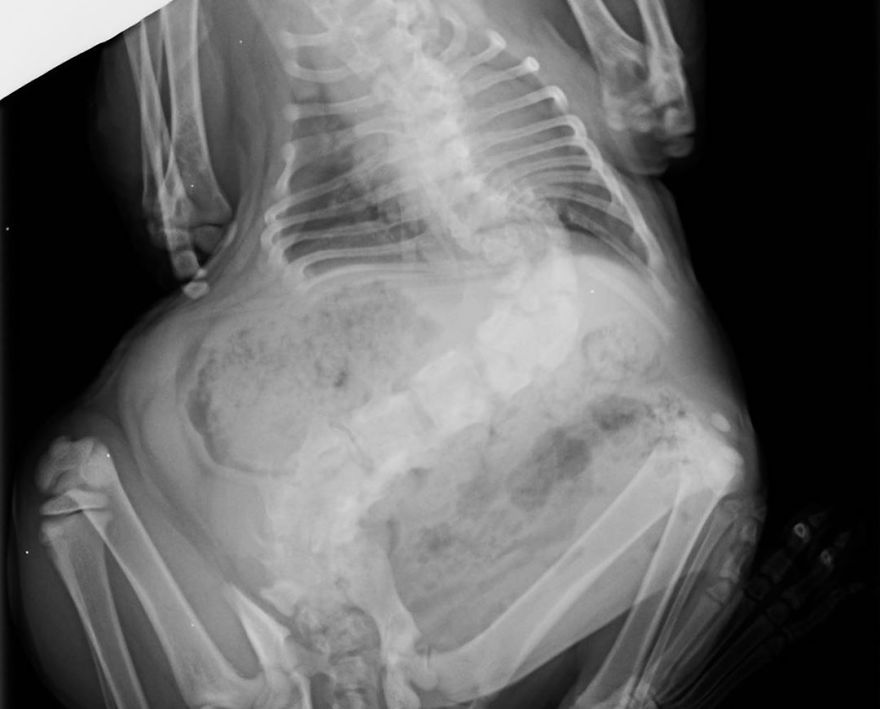

Interview With OwnerThis adorable kitten has a rare spine condition called scoliosis, which makes her spine twisted. The cat was about to be euthanized when she was saved by the vet and given a forever home. A girl named Mari posted on Reddit (Reddit name MarieGotLost) about her grandparents’ adorable pet named Pitoe.

The images got tons of likes and comments. A lot of people sent love to Pitoe, however a lot of them expressed concern about Pitoe’s size and shape. Mari explained that she only looks fat because of her condition and that she lives a happy, healthy, and pain-free life.

Here’s the story of how the 4-year-old Pitoe joined Mari’s family: “So, Pitoe has severe scoliosis, which makes her body a lot shorter than any normal cat’s. (And because of that, she has grown a lot more in width.) She’s actually my grandparents’ cat. My parents are veterinarians and one day someone—who sells cats—brought in a ‘bad litter’ of cats and they had a lot of issues. Pitoe was one of them. The owner intended to have her put down because who would want a cat like this?”

Mira shared some issues they run into because of Pitoes condition: “In all honesty, we expected Pitoe to do a lot worse, but she’s actually just fine part from being a crooked little thing. She is pain-free and active. The biggest issue she has is that she’s not as mobile as other cats, for example, she can’t jump at all. She does get loads of follow up to ensure she stays okay and is on a diet, to prevent her from getting overweight.”

“She’s absolutely fine! She’s crooked and one of her hind legs isn’t as functional, so she often drags. But she has no pain, which is the most important. We do need to keep a good eye out, to make sure it stays that way.” – said Mira when asked about the kittens health and well being.